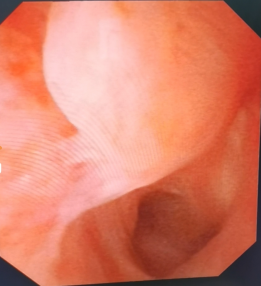

曾铭强 湖南省人民医院泌尿外科主治医师 膀胱尿道造影x线检查发现后尿道闭锁的部位和长度。 三维ct成像显示膀胱尿道的立体结构、与直肠的关系,以及骨盆的稳定性和恢复情况。 车祸、工伤容易导致重要脏器破裂出血、全身多处骨折,如果发生严重的骨盆骨折,还容易并发男性尿道断裂、尿道出血,导致后尿道狭窄或闭锁。发生尿道狭窄的病人,常常出现尿频、尿急、排尿困难等症状,长期梗阻可导致肾功能衰竭等;如果发生尿道闭锁,尿液无法排出,往往需要先行尿流改道、留置膀胱造瘘管,待病情稳定后再接受尿道复通手术。 55岁的黄先生是湖南娄底人,5个月前在工地上被小型挖掘机碾压下腹部,导致骨盆多处骨折、左股骨骨折、失血性休克。在当地医院接受了急诊骨盆骨折固定手术、大量输血等。经过5个月的康复治疗后,患者为求尿道复通手术经当地医生介绍,找到湖南省人民医院泌尿二科曾铭强博士,以“创伤性后尿道闭锁”收住院。 入院后,经过膀胱尿道造影X线检查发现后尿道闭锁的部位和长度,了解了患者尿道损伤部位没有假道、瘘管发生;骨盆和膀胱尿道三维CT成像显示膀胱尿道的立体结构、与直肠的关系,以及骨盆的稳定性和骨折的恢复情况。 术前诊断中,利用膀胱软镜分别从尿道外口进入观察断端远段尿道、从膀胱造瘘口进入观察断端近段尿道的情况,发现前列腺尖部有一片状的结石,也没有发现尿道损伤部位有假道和瘘管形成。通过充分的术前准备后,曾铭强医师等为患者成功实施 “后尿道闭锁段切除+端端吻合术”。术中通过充分暴露、彻底清除瘢痕组织、止血等措施后,行远、近端尿道无张力吻合。 患者术后恢复好,48小时后即可下床适量活动,术后1周出院。